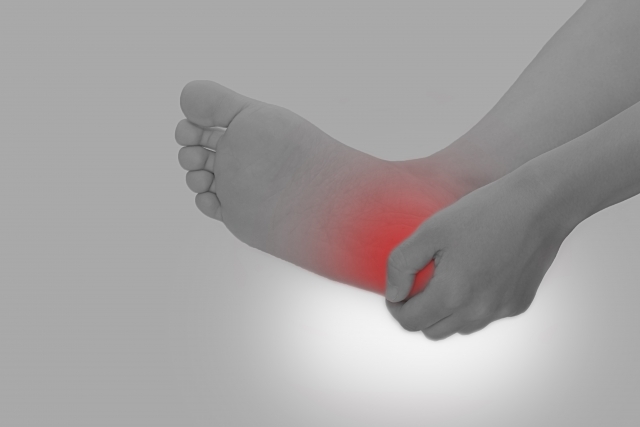

運動していないのに足がしびれる…

腰には問題ないといわれたけど…

足が良くつる…

足の裏に何か張り付いたような感覚がある…

タコやマメ、靴ずれが良くできる…

こんな症状でお悩みではありませんか?

違和感やしびれを感じると気になってお仕事にも中々集中できませんし、何か病気が潜んでいるのではないかと心配になりますよね。

今回はそんな足のしびれや痛みでお悩みの方はぜひ最後まで読んでいってくださいね。最後までお付き合いいただけたら幸いです。

足のしびれやい痛み、違和感は様々なことが原因で起こりますが、中でも今回は糖尿病性末梢神経によって引き起こされる足のしびれや痛み、違和感についてお話ししていきます。

糖尿病性末梢神経障害の症状

糖尿病性末梢神経障害では以下のような症状が出てくることがあります。

足先のしびれ、不快感

足の冷え

手足の感覚が鈍くなる(自覚がない場合が多い)

足底に何か張り付いているような感覚

皮膚を虫が這うような感覚

坐骨神経痛や肋間神経痛、腕や手の神経痛が起きる

足がよくつる

糖尿病性末梢神経障害が原因である場合、左右両方にでることが特徴です。